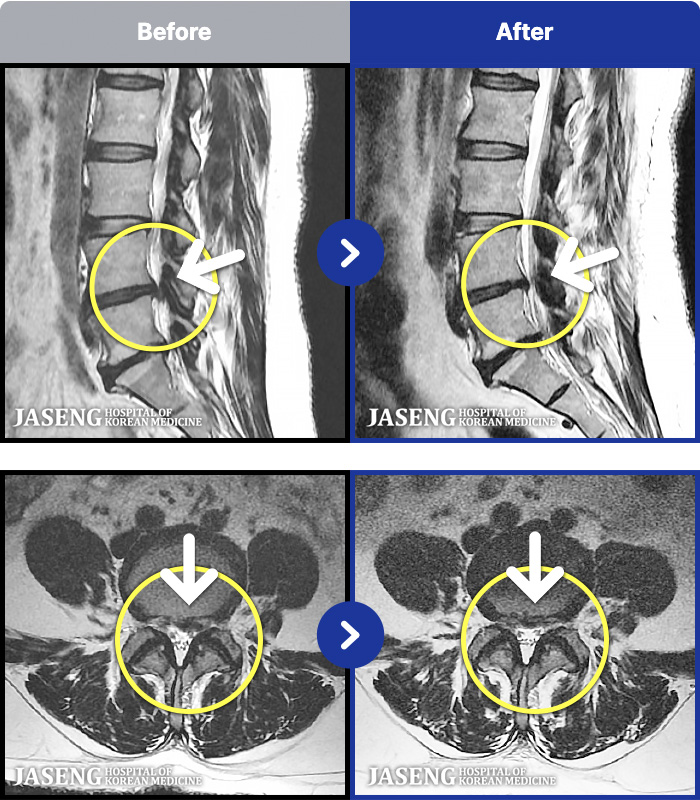

MRI ġ

1,301 MRI ũ ʸ Ȯϼ.